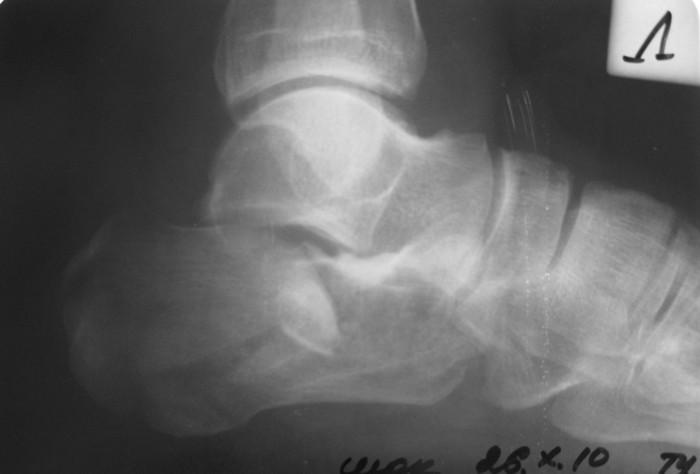

Разница между информацией полученной Р-графески и КТ - огромная.

Пример.

PDF, 134 Kb

Б-ной прооперирован по АО, применялась аутопластика из крыла подвздошной кости. На фото больной через 1 мес. Через 4 мес. - физический труд, осмотр через год - жалоб и претензий нет. До нас обращался в два лечебных учреждения, перелом не диагностирован. Был суд. Пациент процесс выиграл.

Больной гражданин РФ. Травма в Казахстане, здесь же и оперирован.

Виктор.

Во время операции была восстановлена суставная поверхность пяточной кости, после чего появилась надежда на восстановление нормальной функции подтаранного сустава. Кроме того, заполнена аутотрансплантатом критическая полость тела пяточной кости, которая хорошо вида на КТ.

В чем был смысл демонстрации? Диссонанс данных Р-граммы и данными КТ, операции.

Уверен, что без операции функционально результат был бы хуже (внутрисуставной перелом со смещением отломков), рентгенологически - без пластины пяточная кость смотрелась бы симпатичнее.